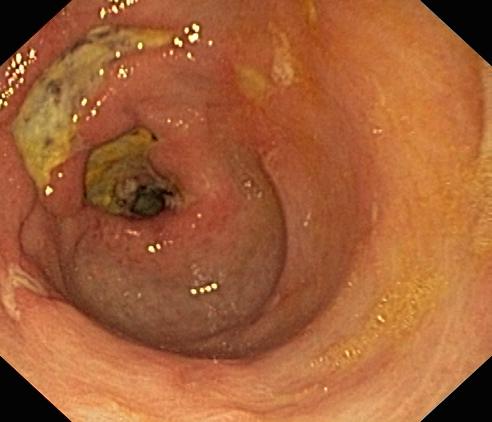

Wrzód trawienny